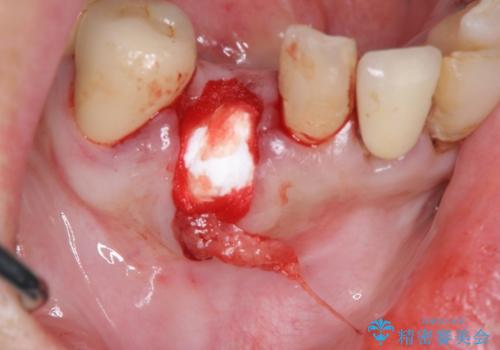

抜歯後、インプラントによる審美・機能改善を希望されたのでインプラント埋入に先立ち吸収した骨の再生を計画します。

歯を失う原因が虫歯や根尖病変などはなく、歯周病や歯の破折等周囲の骨を吸収する原因の場合はインプラント治療を行うに先立ち骨の造成が必要なことがあります。